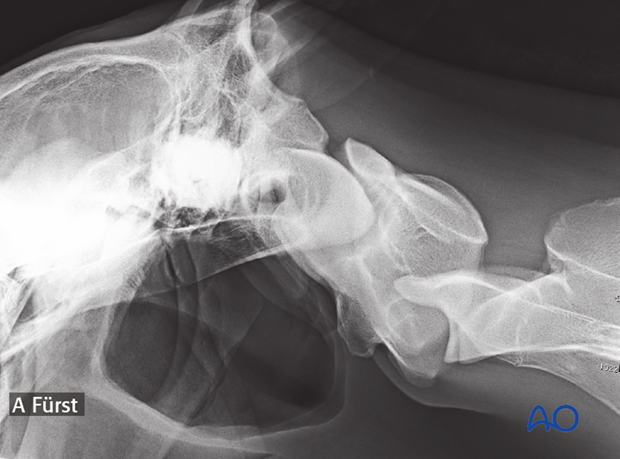

On plain radiographs, there is malalignment of the atlas and axis.

2-year-old patient with a subluxation in C1-C2.